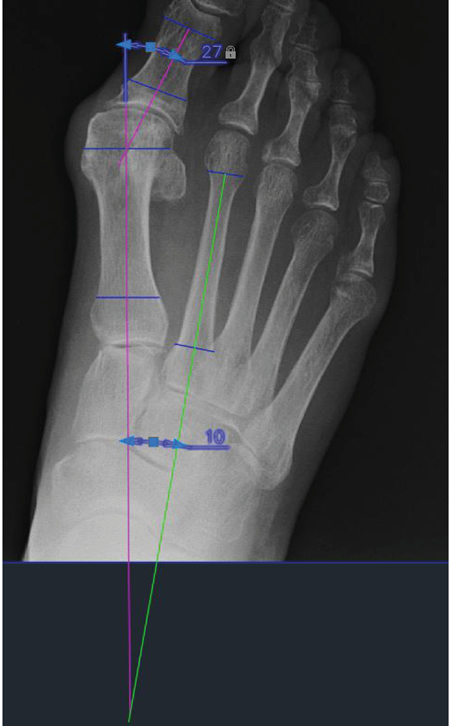

b) Mediciones radiográficas: Estas medidas son las realizadas en las radiografías dorsoplantares en carga prequirúrgicas y postquirúrgicas a los 6 meses.

El aparato de rayos utilizado es una unidad portátil de rayos X-Mind AC® con colimador. Los casettes utilizados han sido Kodak X-Omatic® de 18 x 24 cm con pantalla de intensificación regular y película de color azul, escogidos de este tamaño porque permiten la realización de una proyección dorsoplantar en carga del pie. Cada radiografía ha sido previamente digitalizada utilizando el escáner Epson Expression 1680 Pro®, con capacidad para explorar imágenes en films positivos. Una vez se obtiene la imagen radiográfica digital, se realizan las mediciones con el software AutoCAD® 2022 (Autodesk Inc, San Rafael, California, EE. UU.).

Como se observa en la Figura 3, los ángulos medidos en este estudio han sido: el ángulo hallux valgus o ángulo metatarso-falángico del primer dedo (AHV) y el ángulo intermetatarsal entre primer y segundo metatarsiano (AIM). Ambos ángulos han sido escogidos por ser los más empleados y relevantes para la valoración de la deformidad HAV.

Figura 3. Nuevo instrumento de medición de la movilidad del primer radio.